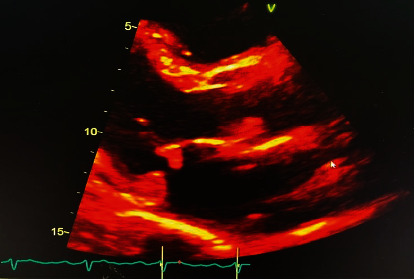

Abstract Image